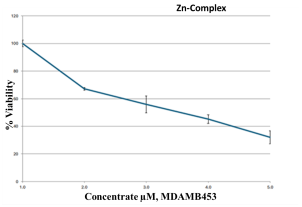

2.9. Cell Proliferation Assessments

| Parameter | Dilution Used to Treat the Cells with the Metal Complexes/µg | ||||

| Zn–ligand complex 2:1 |   | ||||

| Drug conc µg | 0 | 2.5 | 5 | 10 | 20 |

| Mean—blank | 100 | 67.1 | 55.7 | 45.2 | 32.1 |

| Standard deviation | 2.45 | 0.92 | 6.14 | 3.17 | 4.80 |

| HEK293 | - | - | - | - | 67.77 ± 5.875 |